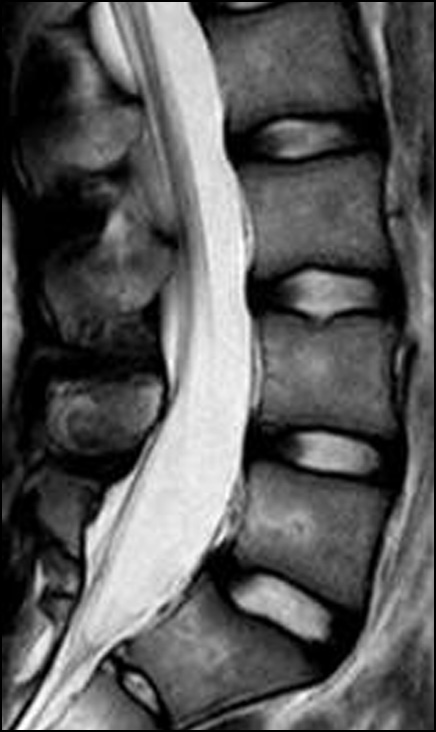

По данным мультиспиральной КТ пояснично-крестцового отдела позвоночника определяется билатеральный спондилолизный дефект межсуставной части дужки L4, L5 позвонка. Стадию спондилолиза, согласно классификации, предложенной К. Fujii и соавт. [13], можно отнести к завершённой на обоих уровнях (рис. 2). Также по данным рентгенографии и КТ отмечаются диспластические изменения задних элементов L5 позвонка в виде асимметрии дужки и изменённой формы остистого отростка. По данным МРТ пояснично-крестцового отдела позвоночника, признаки стеноза позвоночного канала отсутствуют, гидрофильность межпозвонковых дисков не нарушена (Pfirrmann — 1) (рис. 3).

Рис. 3. МРТ поясничного отдела позвоночника, сагиттальный срез.

Fig. 3. MRI of the lumbar spine, sagittal slice.